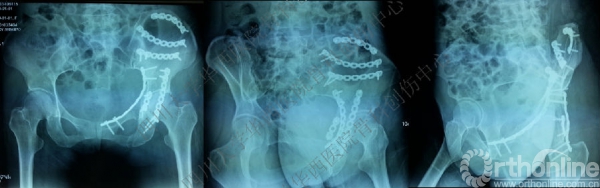

术前CT

入院后行左股骨髁上牵引,积极术前准备,做CT,证实双柱骨折的诊断。